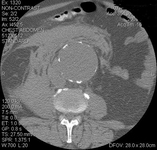

Tomografía computarizada de un AAA roto

University of Michigan, específicamente los casos del Dr. Upchurch que reflejan los Departamentos de Cirugía Vascular y Radiología